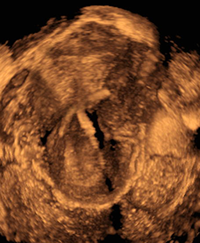

Cardiac teratoma and pericardial effusion.